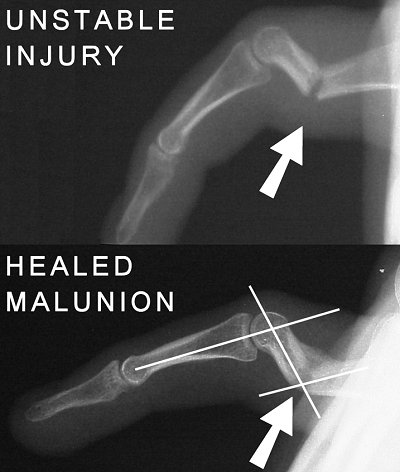

Figure Legend: Unstable phalangeal fractures

follow a predictable course regarding three complications. First, dorsal-palmar

angulation of mid shaft phalangeal fractures occurs due to asymmetric pull

of muscle tendon units. Proximal phalanx fractures typically fall

into a dorsal concave ("apex volar") angulation. Second, failure of reduction

often results in complete recurrence of fracture deformity. Third,

tendon imbalance due to malunion in angulation results in joint contractures

distal to the fracture equal in magnitude and opposite and direction as

the malunion. The top radiograph demonstrates initial angulation of such

a fracture. The fracture was reduced and stabilized with Kirschner

wires, but redisplaced after the original surgeon removed the fixation.

The bottom radiograph demonstrates the healed malunion, complete recurrence

of the initial deformity, with a flexion contracture of the proximal interphalangeal

joint equal in degree to the angle of malunion.